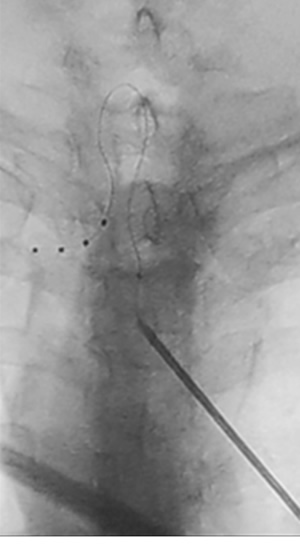

La técnica del implante es prácticamente idéntica a la de la ECP, con la única diferencia de la necesidad de utilizar unas vainas que rodean al electrodo dentro del espacio epidural y nos permiten emplazar el extremo de este en el espacio periganglionar, y la conveniencia de realizar un doble bucle en el electrodo para conferirle estabilidad (Figura 1). El generador del que disponemos es no recargable, requerimos una amplitud de pulso menor que la de ECP, unos 0,8 miliamperios de media, y una frecuencia de 20 hercios. Estas diferencias en la técnica incrementan la complejidad y duración del procedimiento, pero no hay hasta ahora evidencia de mayores complicaciones (6,7). El aprendizaje de la técnica requiere un training en un centro de amplia experiencia, el cual, en el caso del implantador de los casos descritos en este trabajo, fue efectuado de la mano del Dr. Isaac Peña en la Unidad del Dolor del Hospital Virgen del Rocío de Sevilla.

Fig. 1. Imagen de emplazamiento del electrodo de EGRD